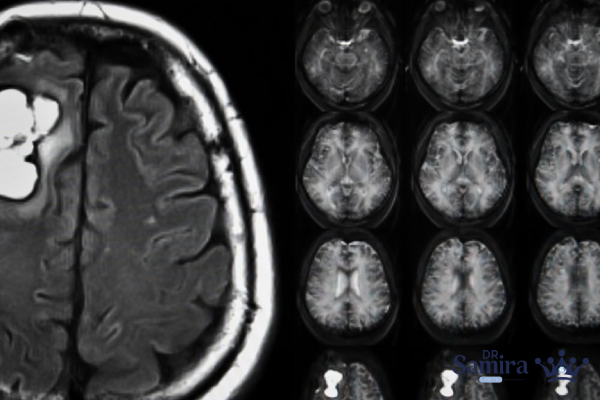

روشهای تشخیص و بررسی تصویربرداری

برای تشخیص دقیق این تومور، تصویربرداری نقش اساسی دارد. MRI با تزریق ماده حاجب، ابزار انتخابی پزشکان است. در MRI تودهای با حدود مشخص و جذب بالای گادولینیوم مشاهده میشود که در داخل یا اطراف سینوس کاورنوس قرار دارد. شکل تومور ممکن است نامنظم باشد و گاهی بخشی از دیواره شریان کاروتید را درگیر کند. CT Scan نیز در مواردی که لازم باشد وضعیت استخوانهای قاعده جمجمه بررسی شود، بهکار میرود؛ زیرا مننژیومها غالباً باعث کلسیفیکاسیون یا تغییرات استخوانی خفیف میشوند.

آنژیوگرافی مغزی نیز گاهی برای بررسی رابطه تومور با شریان کاروتید داخلی و تعیین میزان خونرسانی تومور انجام میشود. این روش بهویژه زمانی اهمیت دارد که برنامه درمانی شامل جراحی یا آمبولیزاسیون باشد. تفکیک مننژیوم سینوس کاورنوس از سایر تومورهای داخل جمجمه مانند شوانوما، آدنوم هیپوفیز گسترش یافته یا تومورهای متاستاتیک اهمیت زیادی دارد، زیرا برنامه درمانی در هر یک متفاوت است.